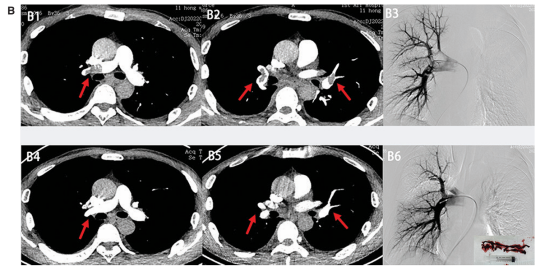

图片图片(Figure2)

Workflow of the Tendvia Mechanical Thrombectomy System.

A) Pre procedure pulmonary arteriography, showing two large clots (clots 1 and 2).

B) A super-stiff guidewire was advanced past target clot 1 via the pulmonary artery.

C) The AGC was delivered along the guidewire to a position near the target clot 1.

D) The Tendvia clot retrieval catheter was advanced along the guidewire and through the AGC to deploy disks into the clot, then retracted into the AGC. After engagement, the clot was extracted through the AGC by suction.

E) The removed clot (target clot 1).

F) The AGC was delivered along the guidewire to a position near target clot 2, and the clot was extracted through the AGC by suction.

G) The removed clot (target clot 2).

H) Post procedure pulmonary arteriography showed no remaining clots. AGC, aspiration guide catheter.